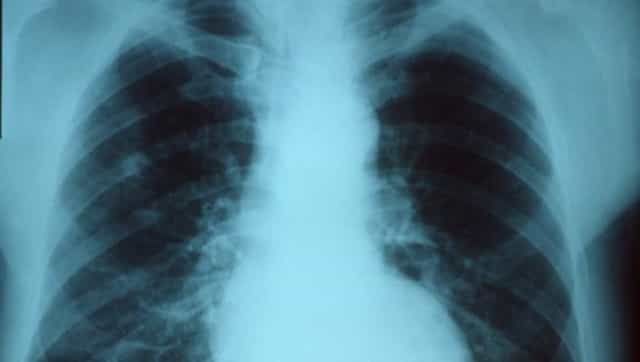

Pneumonia not only causes inflammation in either or both lungs but also leads to the build-up of mucus or fluid in them.